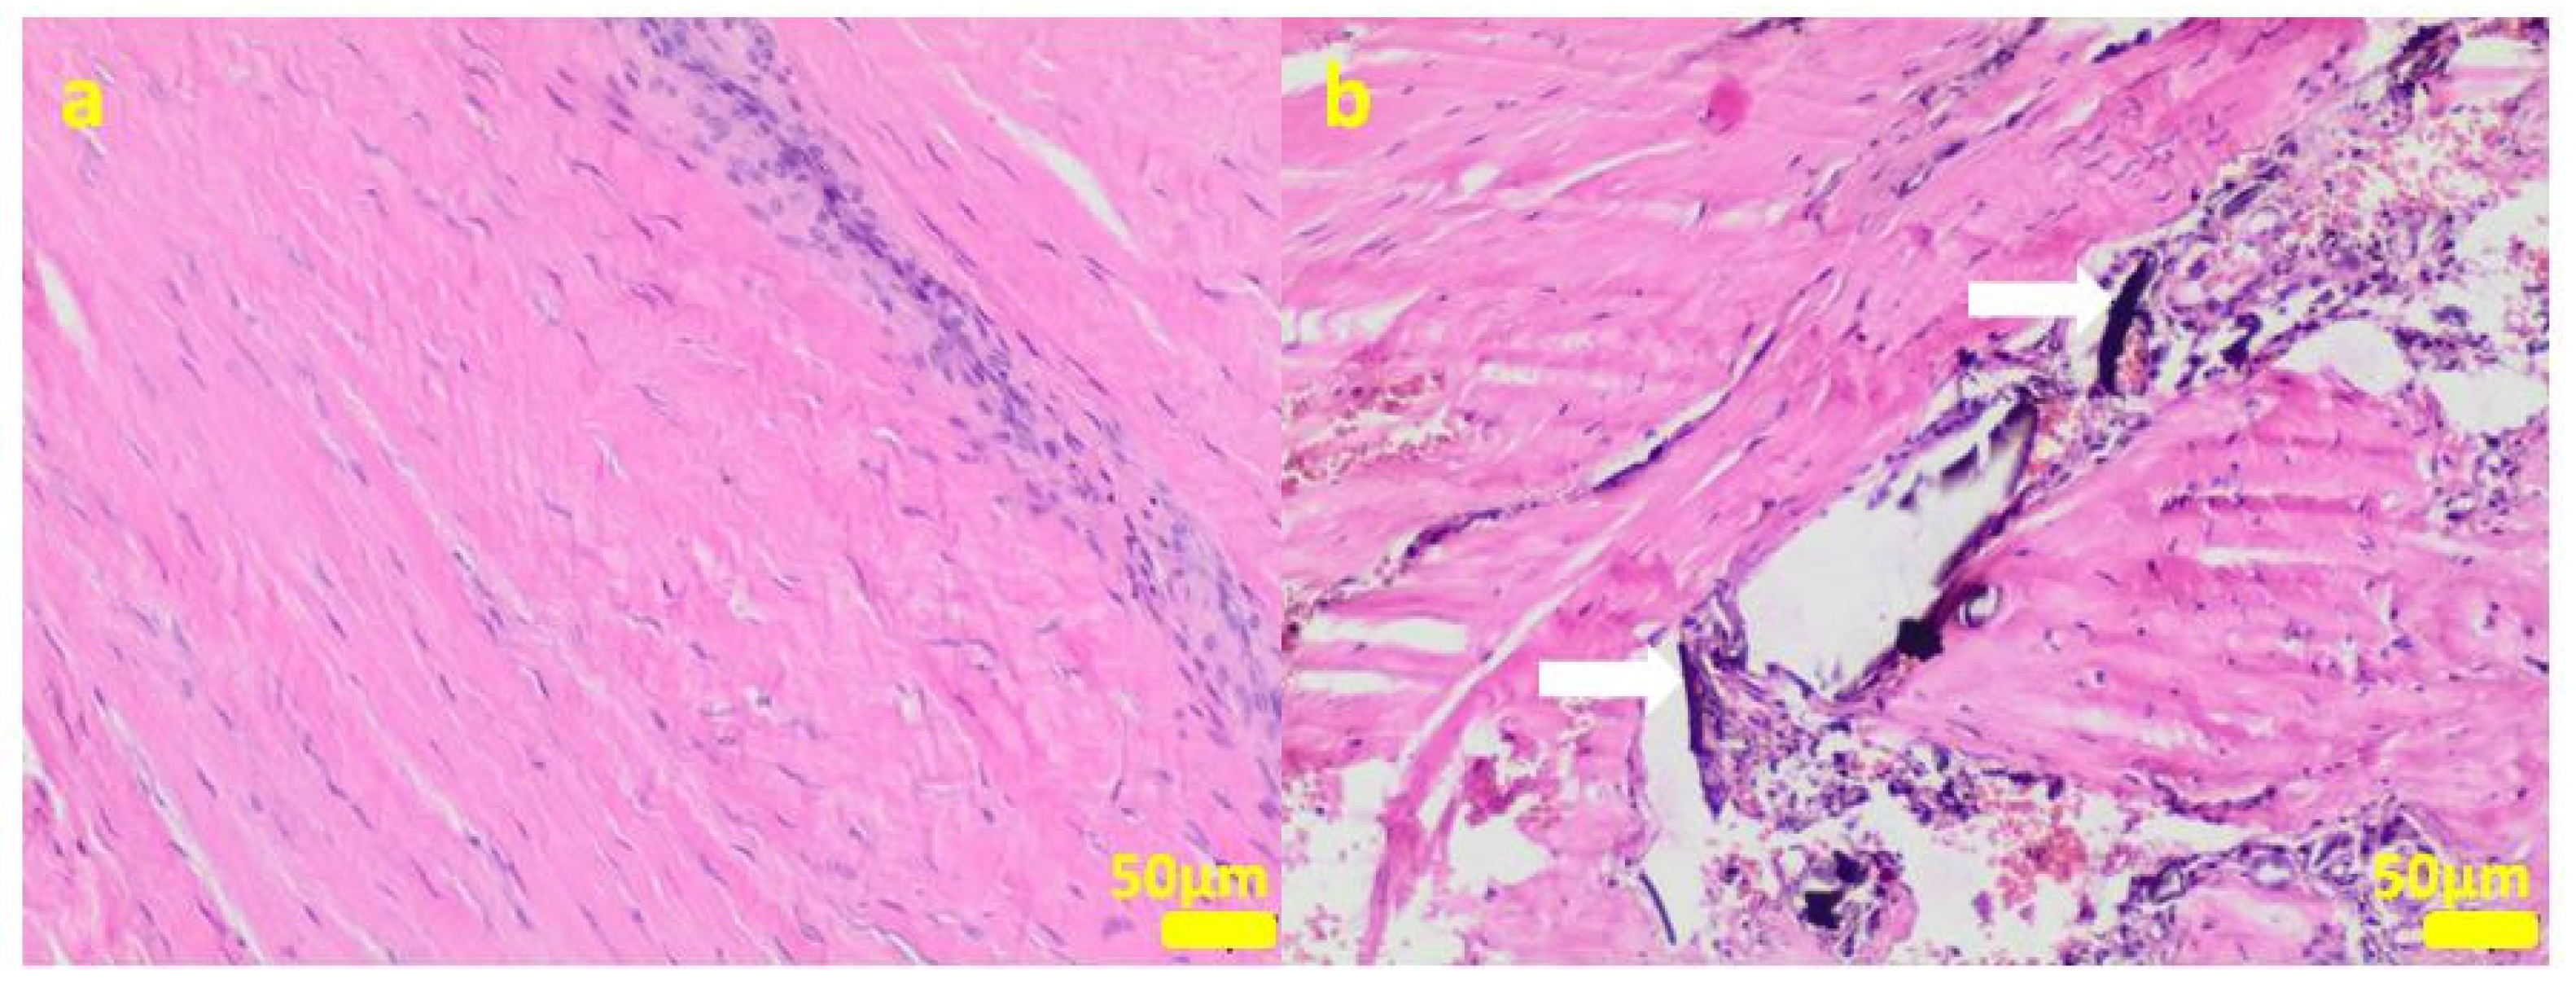

2.1. In Vitro Examinations

2.2. In Vivo Study

4.3. Cell Cultures

4.11. Histopathological Examination